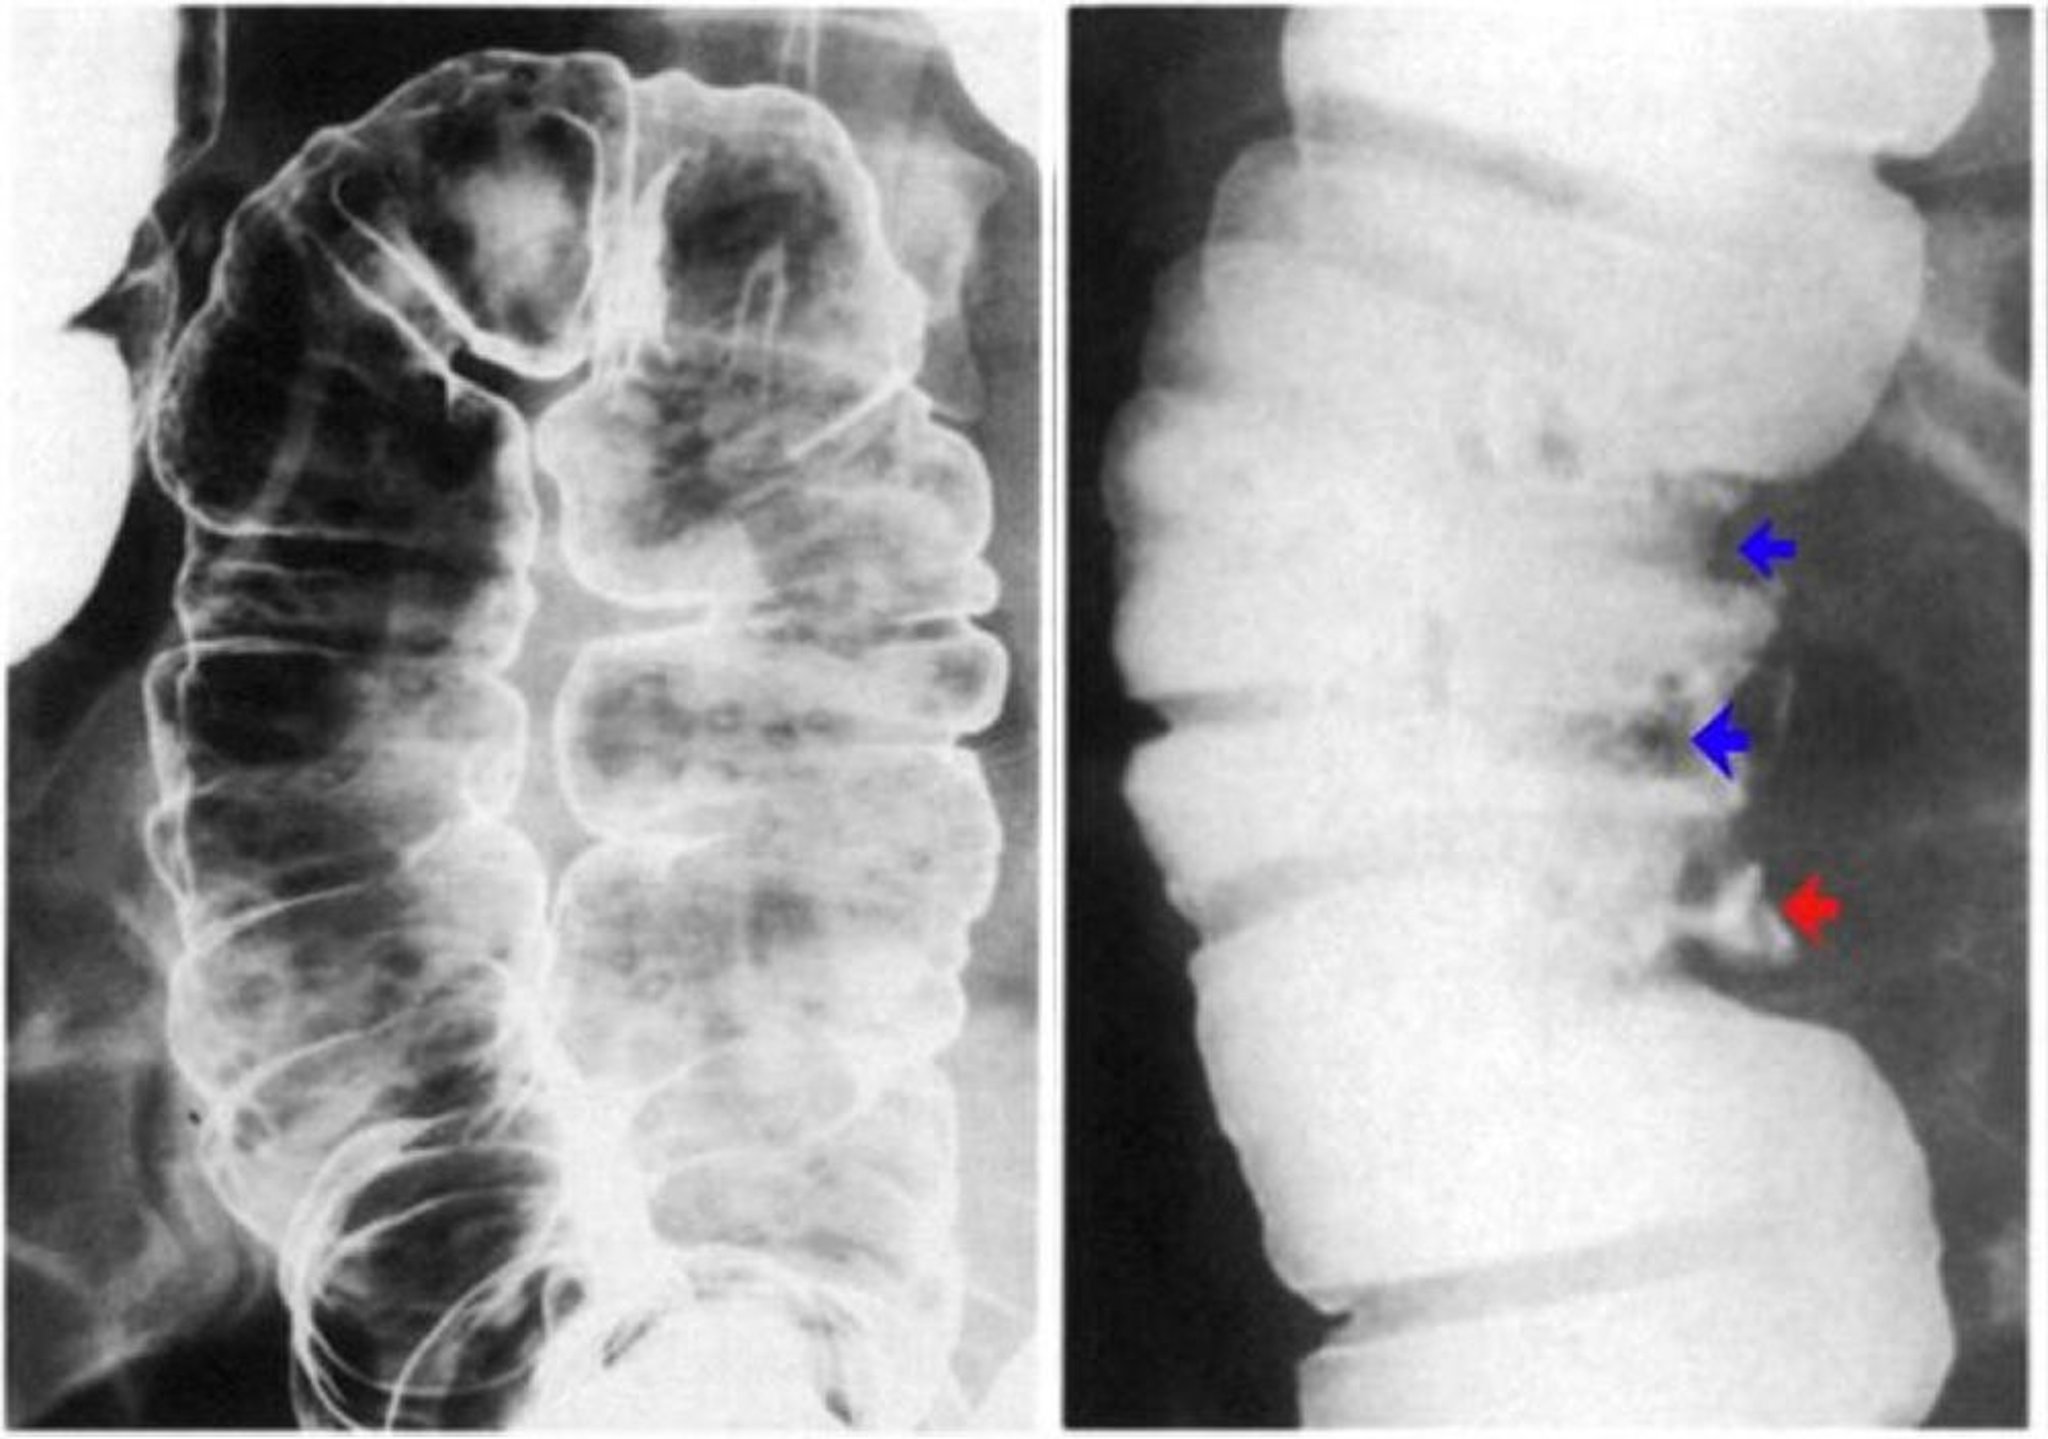

La imagen de la izquierda muestra úlceras aftosas. Se observan erosiones individuales con un halo claro sobre un fondo de mucosa normal. La imagen de la derecha muestra seudopólipos revelados como defectos de contraste (flechas azules) y también una úlcera profunda (flecha roja).